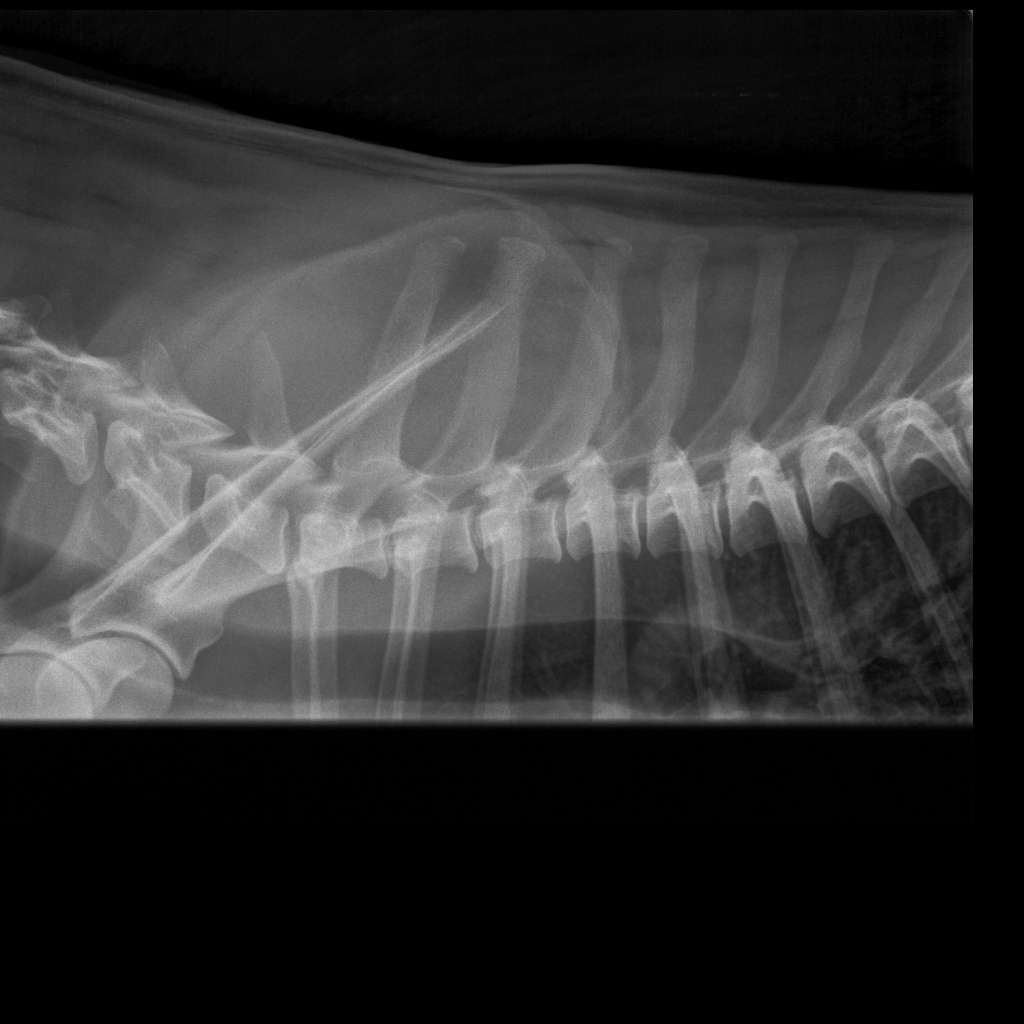

Koko selkä kuvattu terveeksi toistamiseen 1.9.14:

kaularanka

rintaranka

lanneranka

Quti viety lääkäriin, koska vingahtelee kääntäessän päätään. Koko selkä kuvattiin, ei muutoksia. Oireiden jatkuessa kaularanka

magneettikuvattiin. Kuvanneen eläinlääkärin mielestä Nomilla on välilevyrappeuma ja kaikki harrastaminen mietittävä uudelleen.

Halusimme toisen mielipiteen Timo Talviolta, joka halusi ottaa Nomin kaularangasta taivutuskuvat. Talvion mukaan kyseessä ei ole

välilevyrappeuma vaan taivutuskuvissa näkyy kaularangan nikamien 5 ja 6 välillä liukuma. Lääkekuurin ja levon jälkeen voi

harrastamista jatkaa normaalisti. Talvion lausunto:"Kyse on nikamien välisestä "löysyydestä". Selkärangan rakenteelliset

viat ovat pääsäänöisesti perinnöllisiä, mutta tällainen lievä nikamien välinen liikkuvuus ei sellaisenaan ole perinnöllistä,

toki perintötekijät voivat altistaa tämänkaltaisen tilan kehittymiseen."